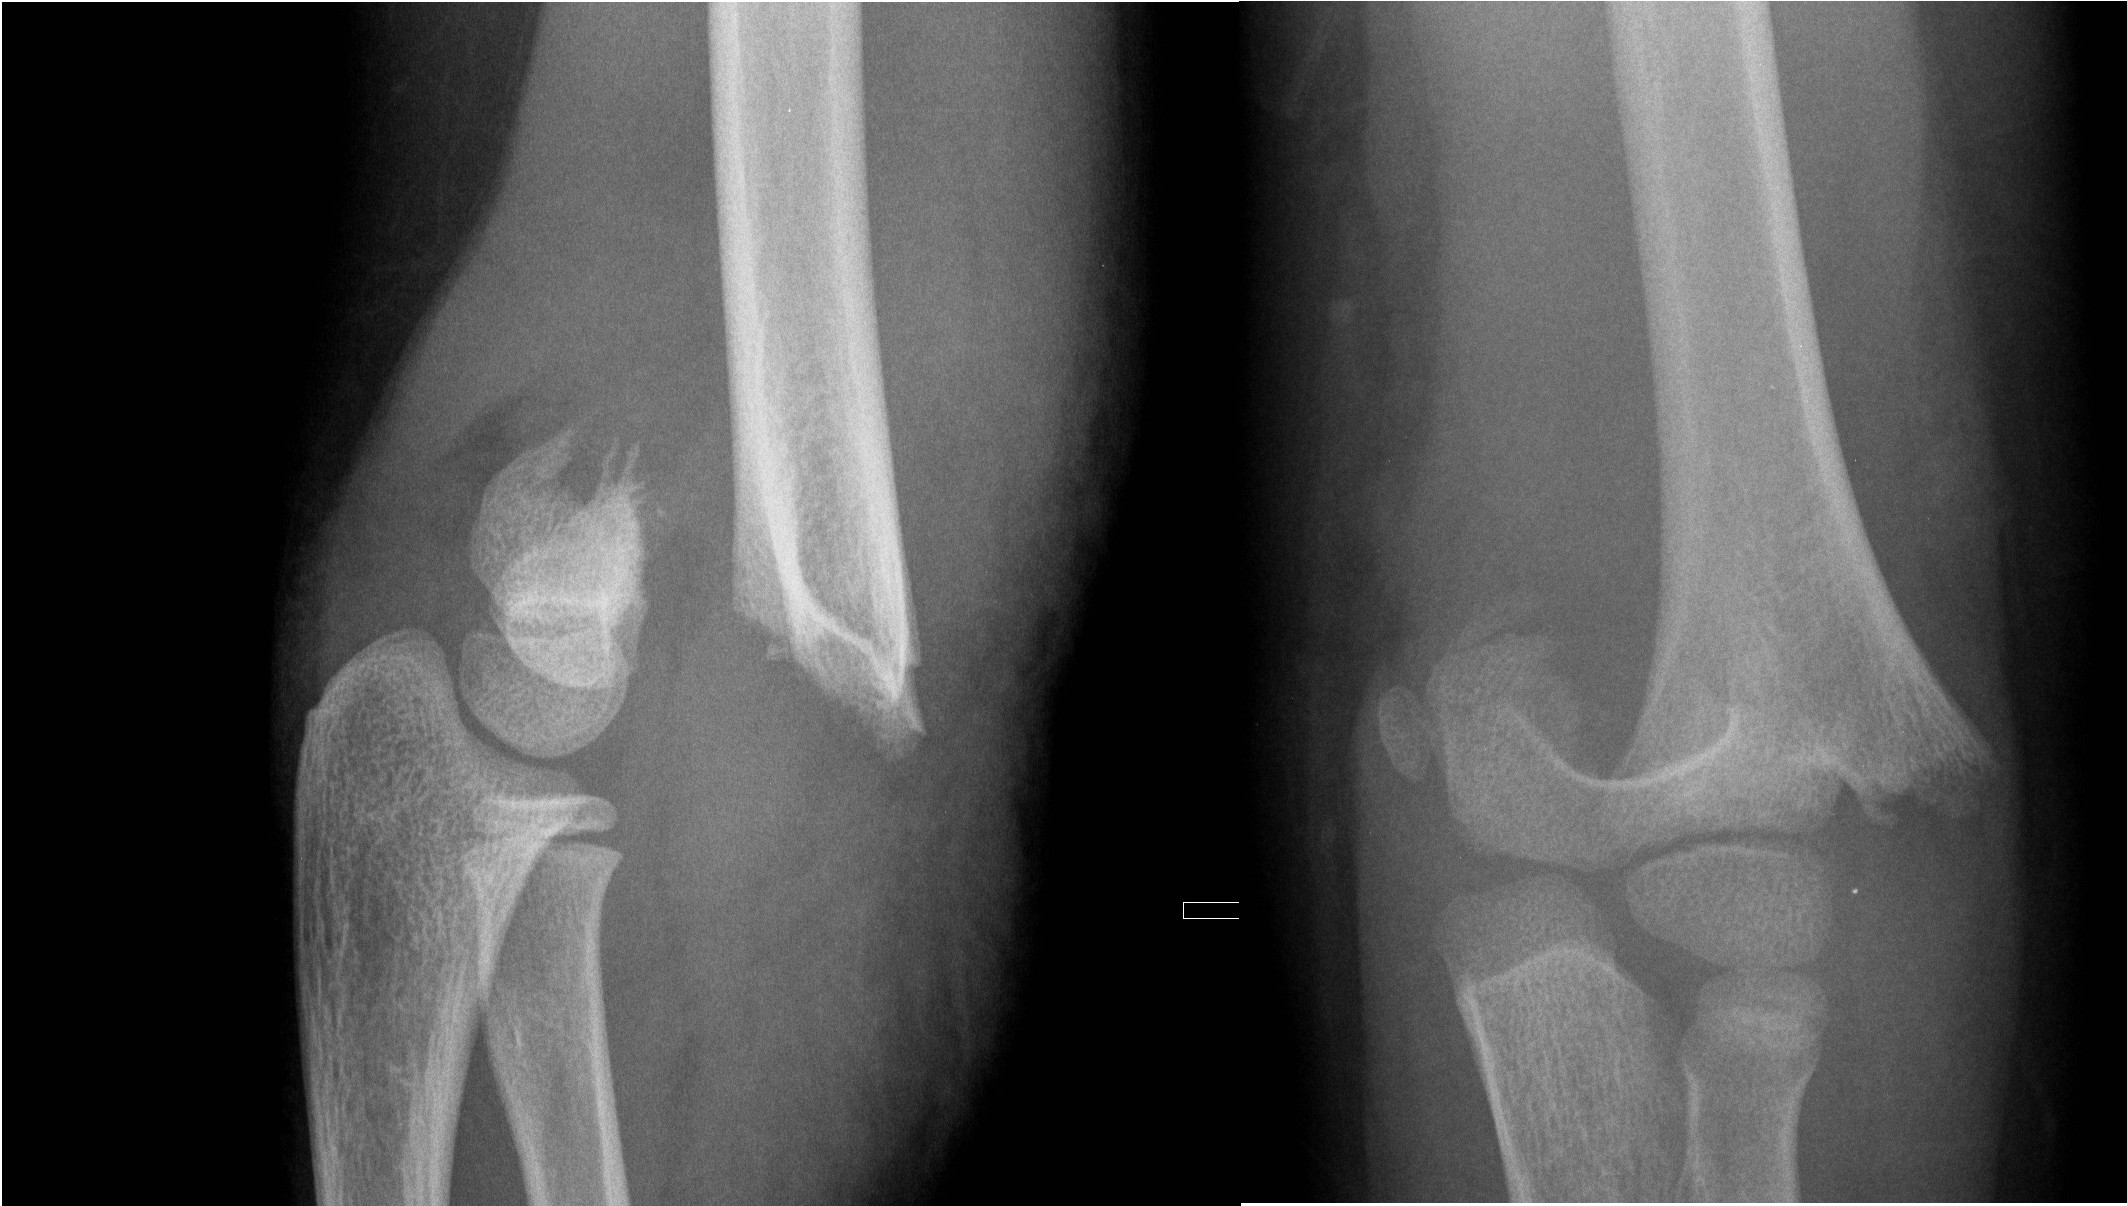

Olecranon fractures

- Olecranon fractures are often seen in combination with other elbow fractures (lateral condyle, supracondylar, radial neck or radial head dislocation).

Undisplaced olecranon fractures

- Above elbow plaster backslab at 90 degrees flexion with Orthopaedic Fracture clinic follow up in 7-10 days.

Displaced olecranon fractures

- Should be discussed with the Orthopaedic team for further management.

Non-displaced Olecranon fracture

Radial Head and Neck Fractures (Proximal Radius)

- Minimally displaced radial head and neck fractures with < 30 degrees angulation

- Displaced fractures or > 30 degrees angulation

- should be discussed with the Orthopaedic team for reduction.

Radial neck fracture